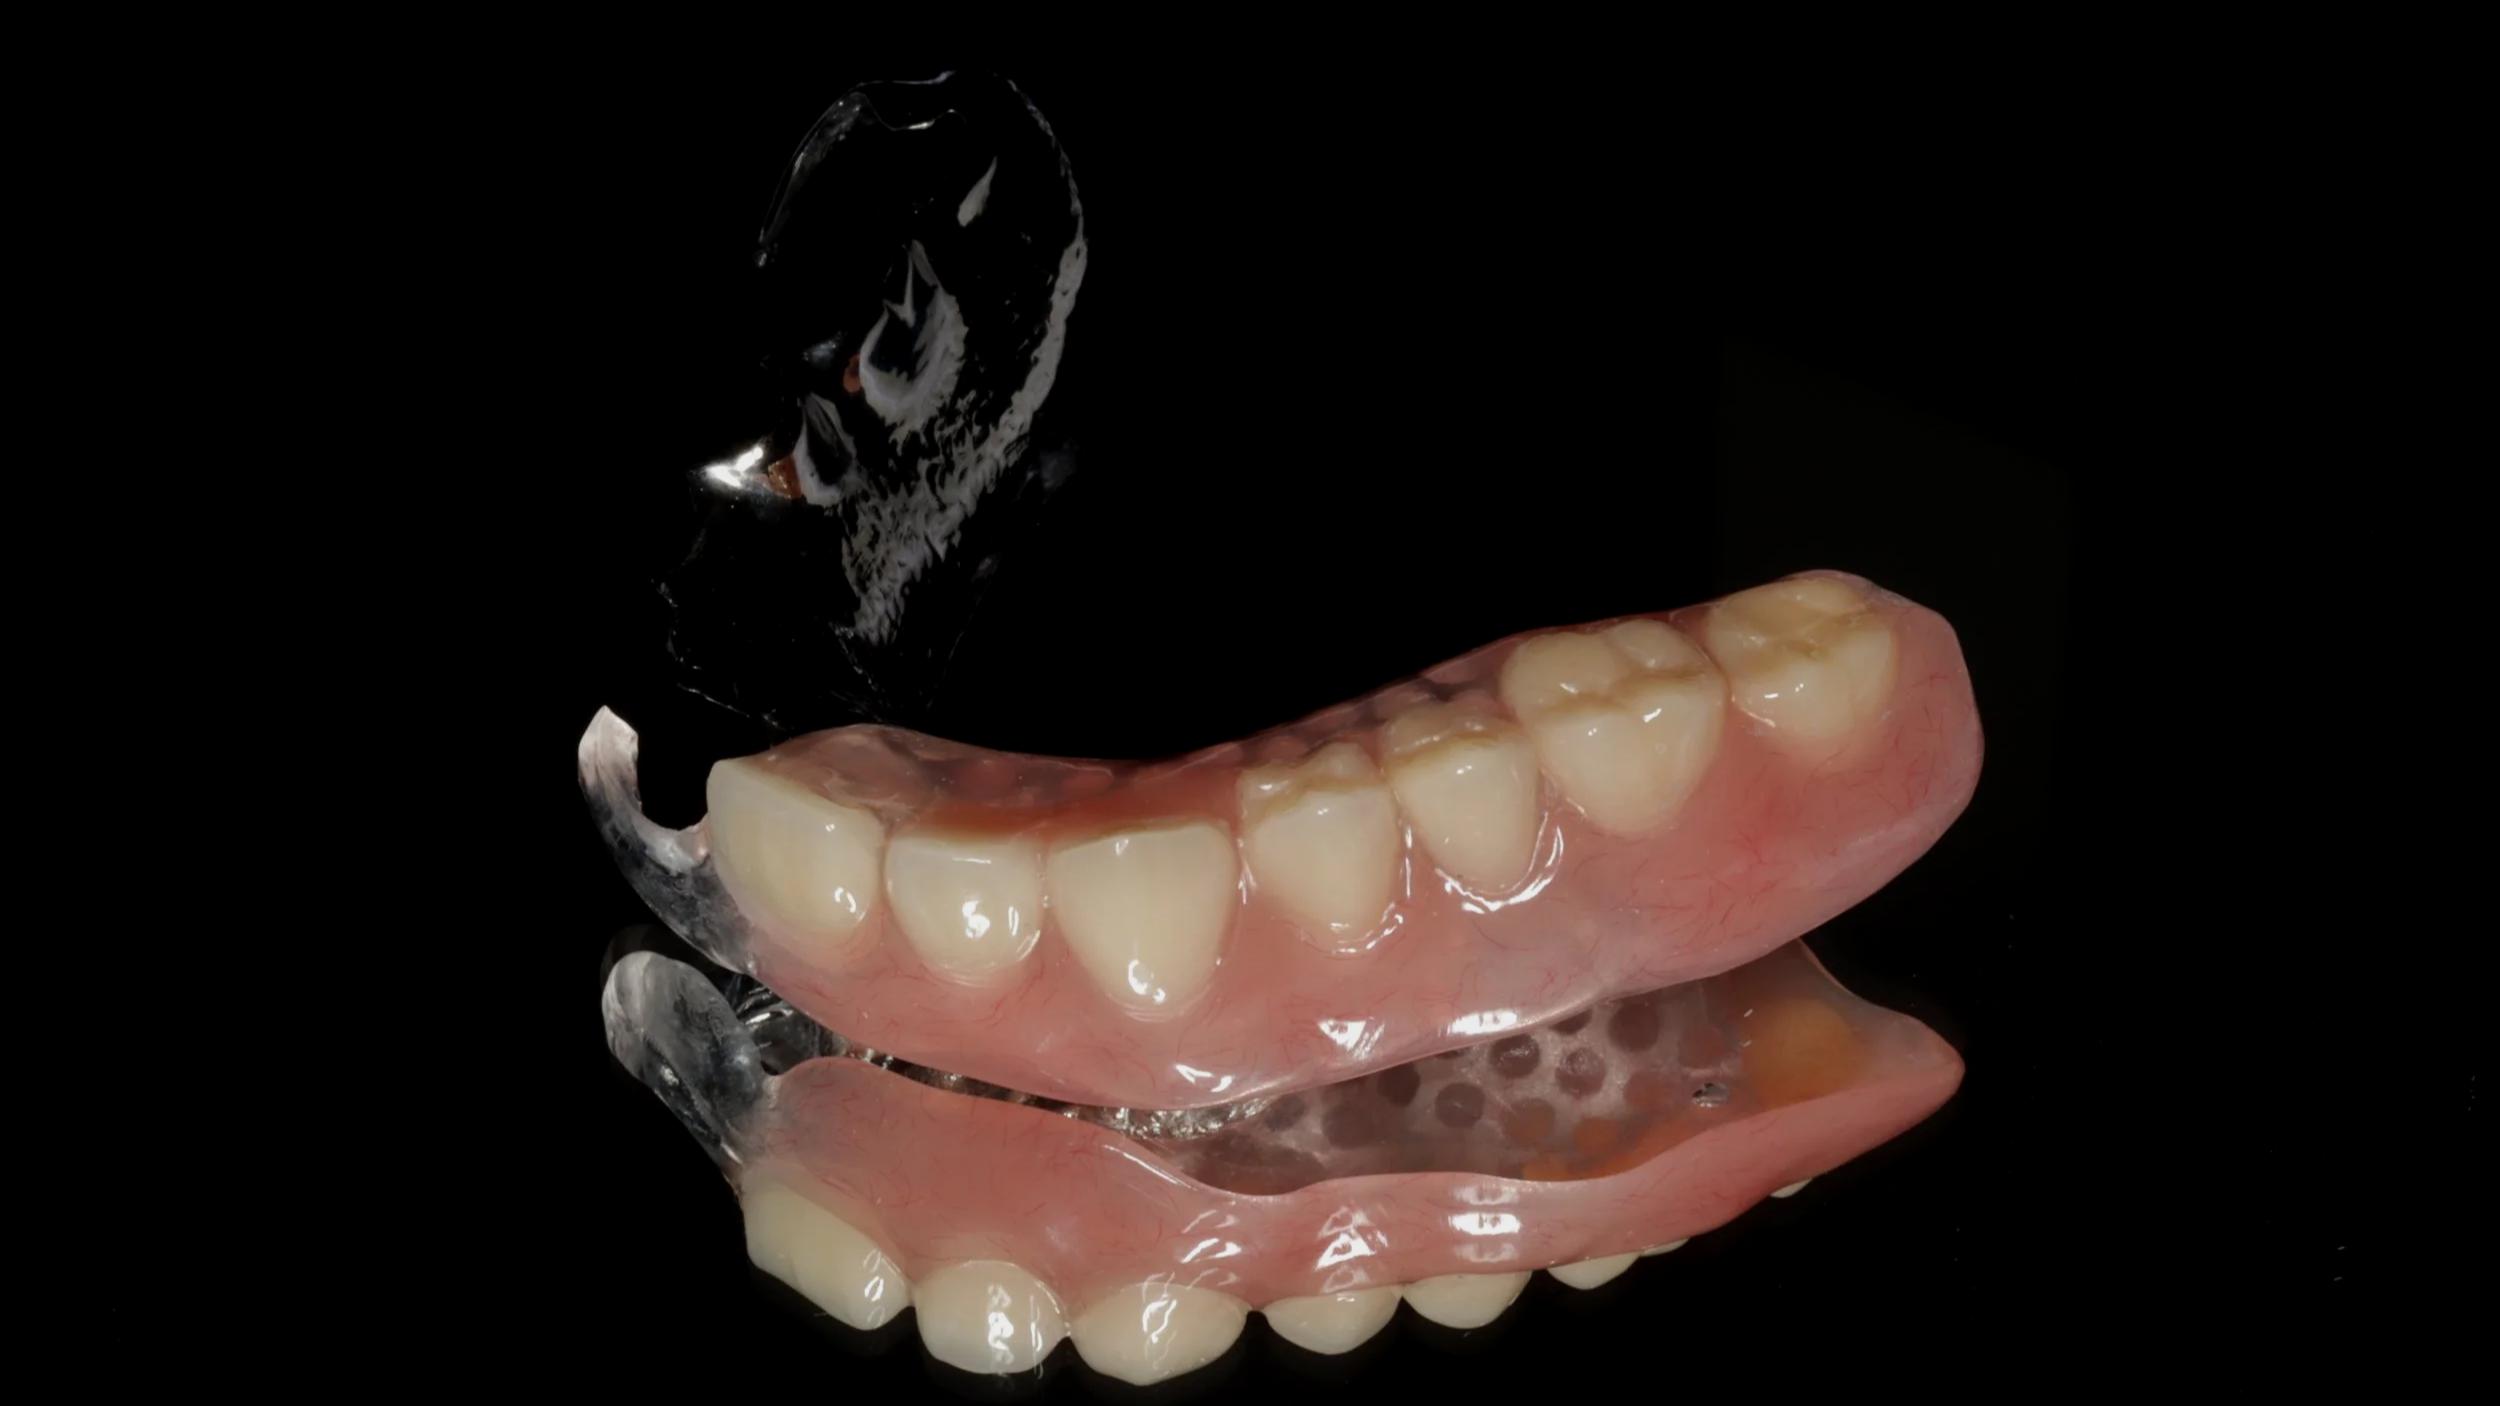

残せる歯は、しっかり根の治療を開始しつつ、新しい入れ歯を装着。内側を金属で薄く作る事で違和感の軽減を図りました。

デジタルデンチャー

内側を金属で薄く作る事で違和感の軽減を図りました。前歯の見える部分は、透明の素材を使用。口の状態によってピンク色のときもあります。